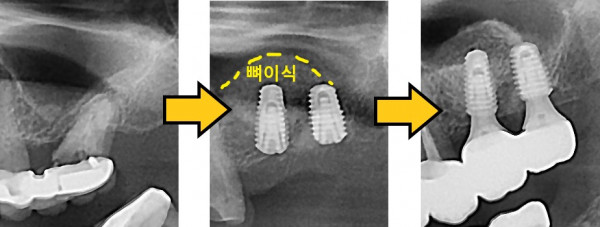

임플란트 뼈이식 + 임플란트